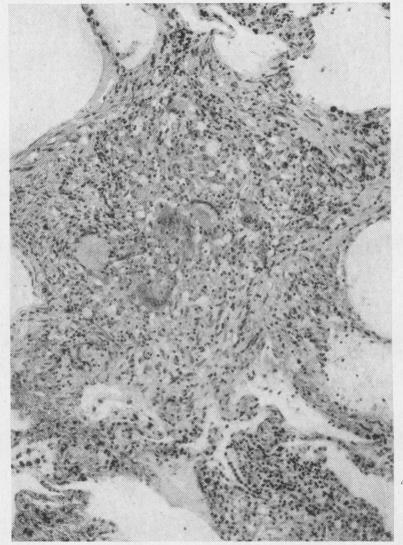

A histological study of the lungs in 52 cases of chronic beryllium disease.

Br J Ind Med. 1958 Apr;15(2):84-91. doi: 10.1136/oem.15.2.84.